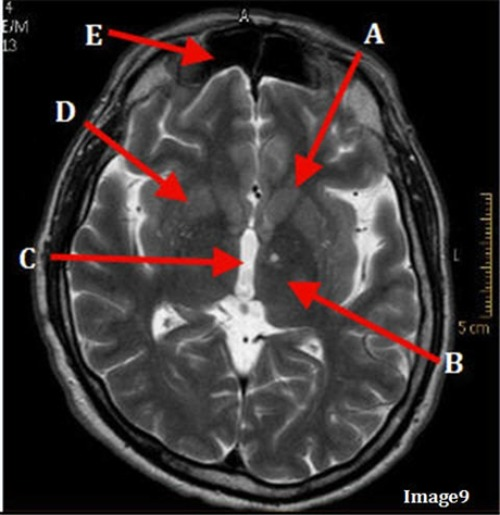

Image 9 is an example of a _____ weighted sequence acquired in the ______ scan plane.

C. T2; Axial

Letter E in Image 9 is pointing to:

C. Frontal Sinus

Letter C in Image 9 is pointing to:

A. Third ventricle

Letter A in Image 9 is pointing to:

D. Caudate nucleus

Letter D in Image 9 is pointing to:

C. Lentiform nucleus

Letter B in Image 9 is pointing to:

B. Thalamus